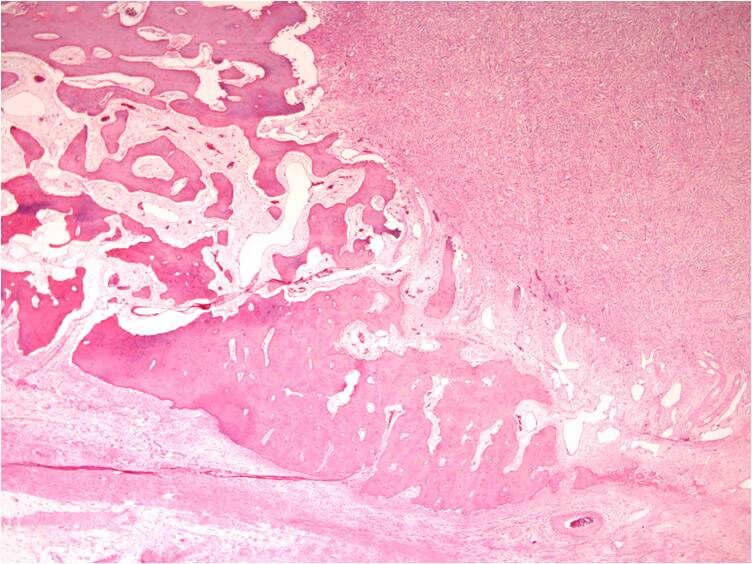

Malignant fibrous histiocytoma of bone is a high-grade spindle cell sarcoma. Microscopically they are heterogeneous fibroblastic tumors formed by poorly differentiated fibroblasts, myofibroblasts, histiocyte-like cells with high degree of pleomorphism, characteristic storiform pattern and also demonstrate bizarre multi-nucleated giant cells (Fig. 7-9).

Fig. 7-9: Microscopic Pathology. Low (Fig. 7), intermediate (Fig. 8) and high (Fig. 9) power magnification H&E slides demonstrate a hypercellular high grade spindle cell sarcoma. Abundant poorly differentiated fibrous tissue is visible in storiform pattern in all magnifications. Multiple giant cells are also seen. Tumor cells are pleomorphic and darkly stained. There are large bizarre appearing cells and atyipical mitotic figures.